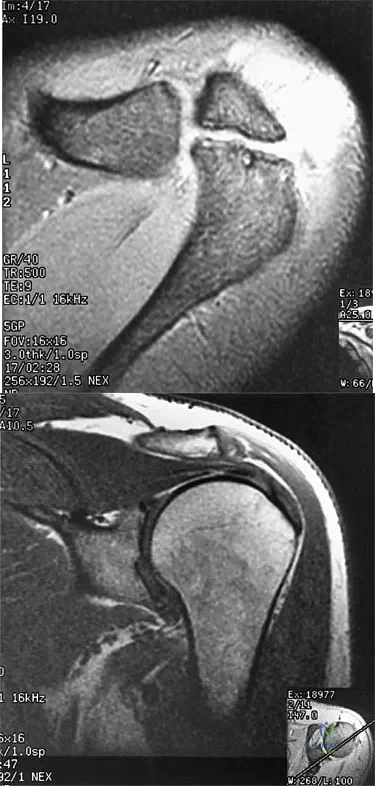

A 47-year-old male tennis player has pain in his nondominant shoulder that has failed to respond to 4 months of nonsurgical management. Examination reveals acromial tenderness and pain at the supraspinatus tendon insertion. He has a positive impingement sign, pain on forward elevation, and minimal cuff weakness. The MRI scans are shown in Figures 30a and 30b. To completely resolve his symptoms, treatment should consist of

Explanation